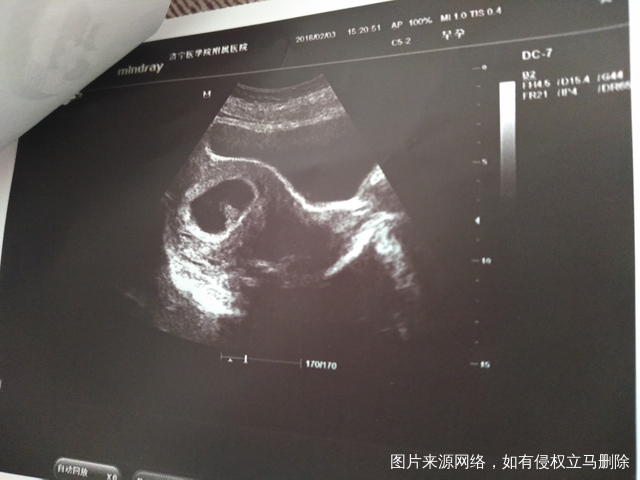

今天是怀孕16周去做了胎心监测还有做了一个B

正常的胎盘附着于子宫体部的前壁、后壁或侧壁,远离宫颈内口。妊娠28周后,胎盘仍附着于子宫下段,其下缘达到或覆盖宫颈内口,位置低于胎儿先露部,称为前置胎盘。你的情况,现在孕周还小,还不能确定是前置胎盘。遵医嘱用药吧!注意休息,观察是否有阴道流血,如果有阴道流血,及时去医院。